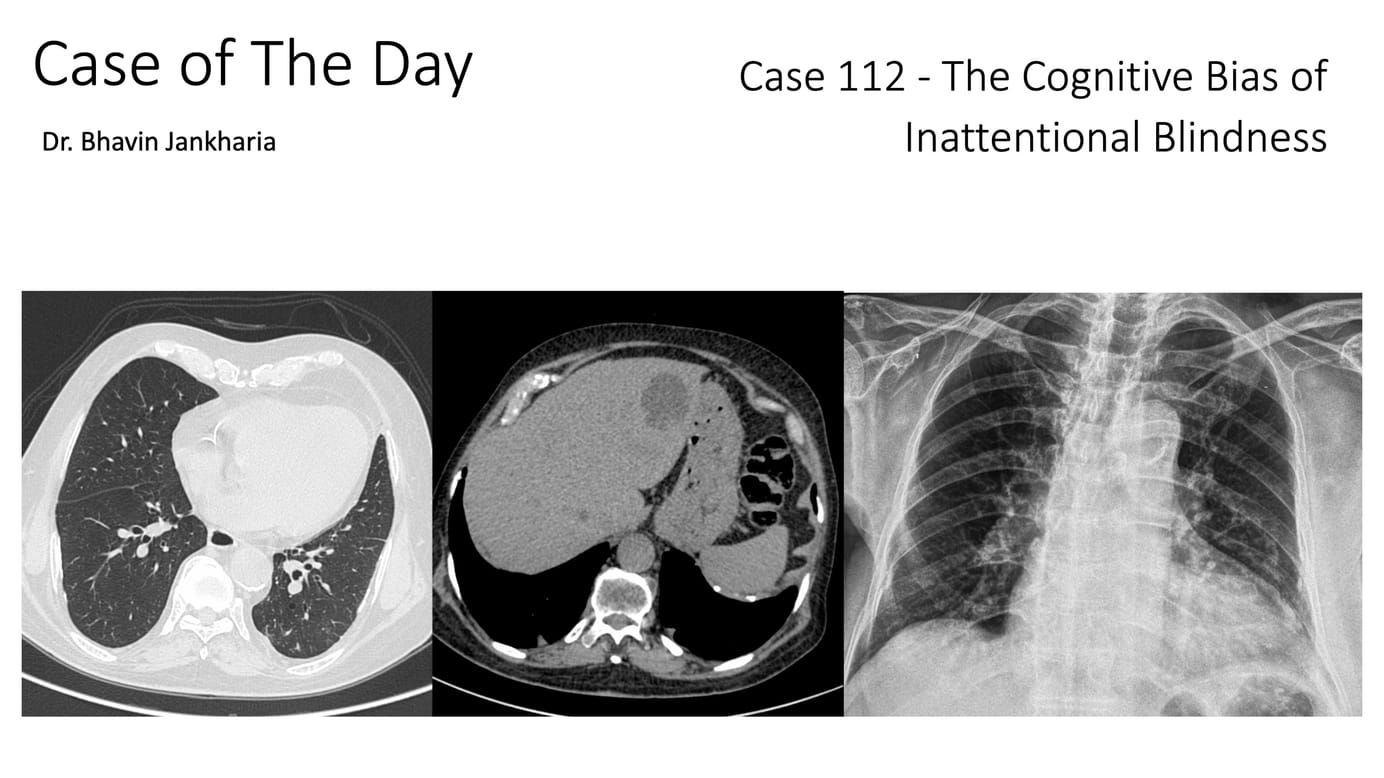

Case of the Day 112 - The Cognitive Bias of Inattentional Blindness Paid Members Public

We need to up our game and pick up all the findings that exist by paying attention to different parts of the chest, scrolling slow and fast and asking ourselves each time whether every area is normal or not